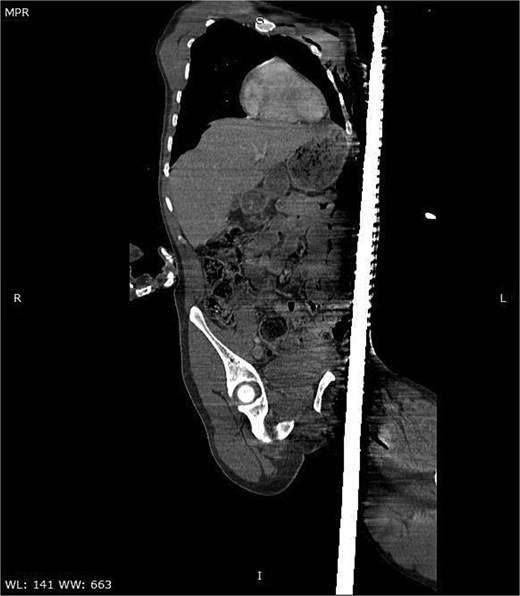

A CT scan of the pelvis, abdomen, and chest revealed the metal rod’s trajectory, penetrating the medial aspect of the left proximal thigh and traversing the left inguinal region lateral to the femoral vessels and nerve, with no evidence of vascular injury or hematoma (Figs 2 and 3). The rod continued through the abdominal wall in the subcutaneous plane without entering the peritoneal cavity, and no free fluid was detected (Fig. 4). It then extended through the left chest wall, associated with subcutaneous emphysema, but no intrathoracic injury was evident.

Sagittal CT image demonstrating the trajectory of the metallic rod traversing the body through the subcutaneous and epifascial planes.